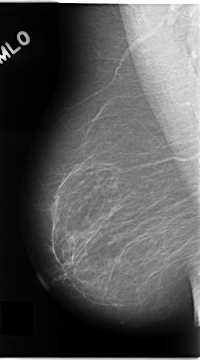

C_0138_1.LEFT_MLO

LEFT_MLO LINES 4720 PIXELS_PER_LINE 2672 BITS_PER_PIXEL 12 RESOLUTION 50 OVERLAY

RIGHT_MLO LINES 4680 PIXELS_PER_LINE 2600 BITS_PER_PIXEL 12 RESOLUTION 50 NON_OVERLAY